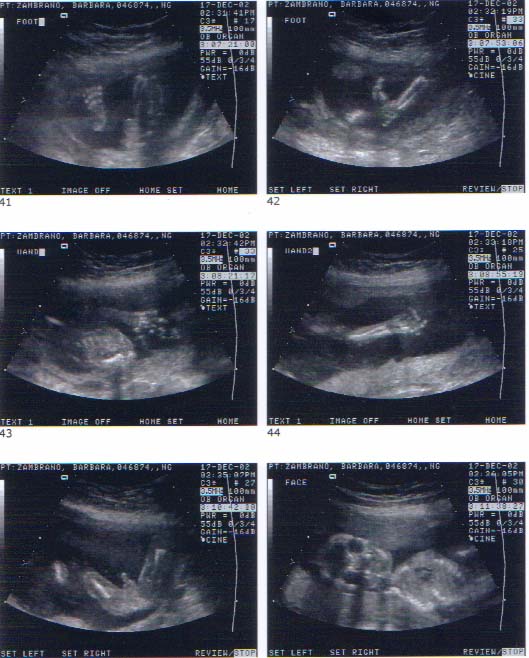

The Zambrano family, including its soon-to-be newest family member, sincerely wish all Trib Times readers a blessed and very merry Christmas and New Year.